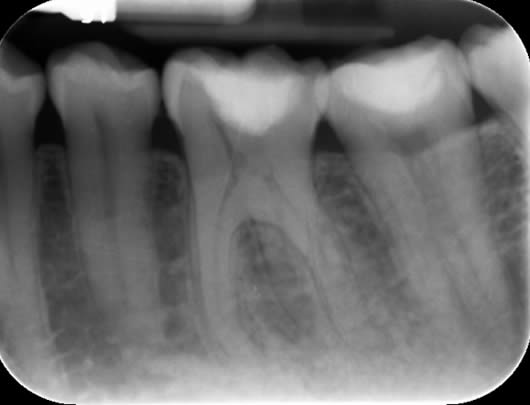

Case 4: Root canal treatment - curved canals.

Some teeth develop with acutely curved roots. These can be very challenging to treat not least because of stresses it puts on the instruments but also, it can be difficult to maintain the shape. The main challenge in this case was the acute curve in the front (mesio-buccal) root. We managed to maintain the shape after careful progression to ensure our files did not fracture.

Before treatment UL6

Following root canal treatment